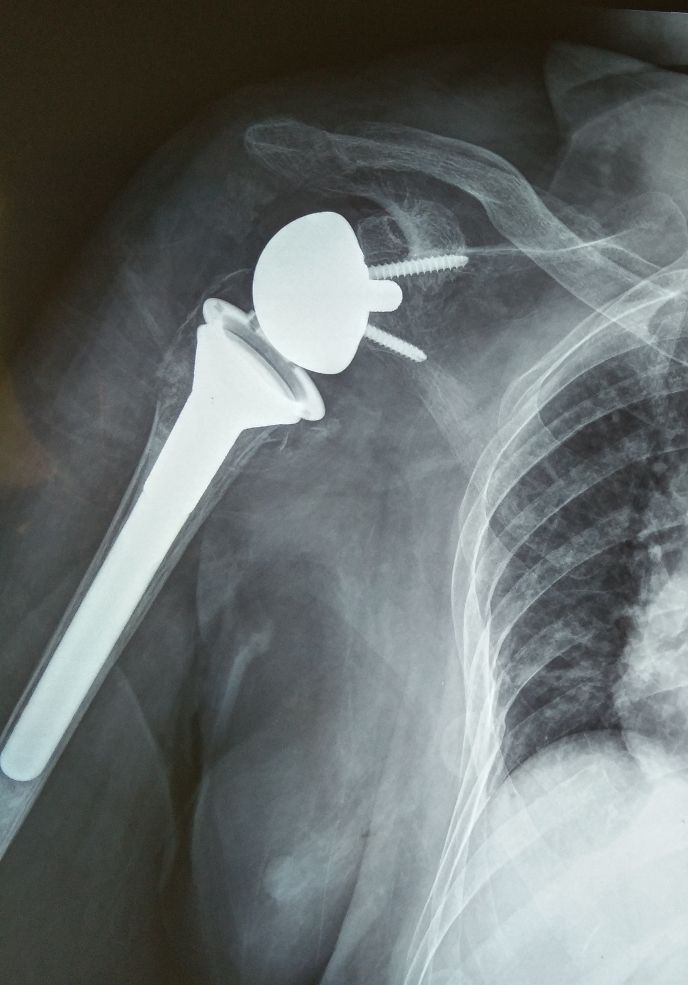

患者女性,83岁,反置式肩关节置换术后15日入院。

这个病例也是一位高龄骨折患者,不过是没有行内固定手术,而是做了关节置换手术。片子上也可以看到患者得骨质疏松情况也是很严重。康复治疗过程中也需要全程关注患者的反应和生命体征情况,个性化治疗,循序渐进来改善患者的患侧上肢功能,逐渐提高患者日常生活能力。